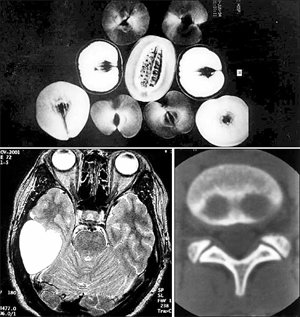

연세대 정태섭 교수는 의료용 진단장비로 촬영한 독특한 사진을 모은다. 위는 과일의 MRI 사진, 아래 왼쪽은 염증 조직이 하트처럼 찍힌 뇌의 CT 사진, 오른쪽은 돼지 코 모양이 나타난 척추의 CT 사진. 사진 제공 정태섭 교수

10년 전쯤 CT 사진을 정리하다 재미있는 파일을 찾아냈다. 암 덩어리가 하트 모양으로 보이는 뇌 단면, 돼지 코처럼 생긴 척추 단면 등 특이한 모양이 찍힌 인체 사진이 들어 있었다. 수많은 환자를 촬영하면서 우연히 이런 사진을 얻을 때마다 모아뒀더니 꽤 많아졌다.

불현듯 환자 대신 사물을 찍어보면 어떨까 하는 생각이 스쳤다. 그때부터 틈날 때마다 나뭇잎, 컴퓨터, 과일 등 주위에서 흔히 보는 사물을 진단장비로 촬영해 보기 시작했다.

과일을 MRI로 찍으면 종류마다 밝기가 다르다. 잘 익었거나 수분이 많을수록 밝다. 노트북컴퓨터나 디지털카메라를 X선으로 찍으면 내부 배선과 회로 구조가 선명하게 나타난다. 의료용 진단장비로 찍은 사진이 사물의 본질을 이해하는 데 도움을 주는 셈이다.